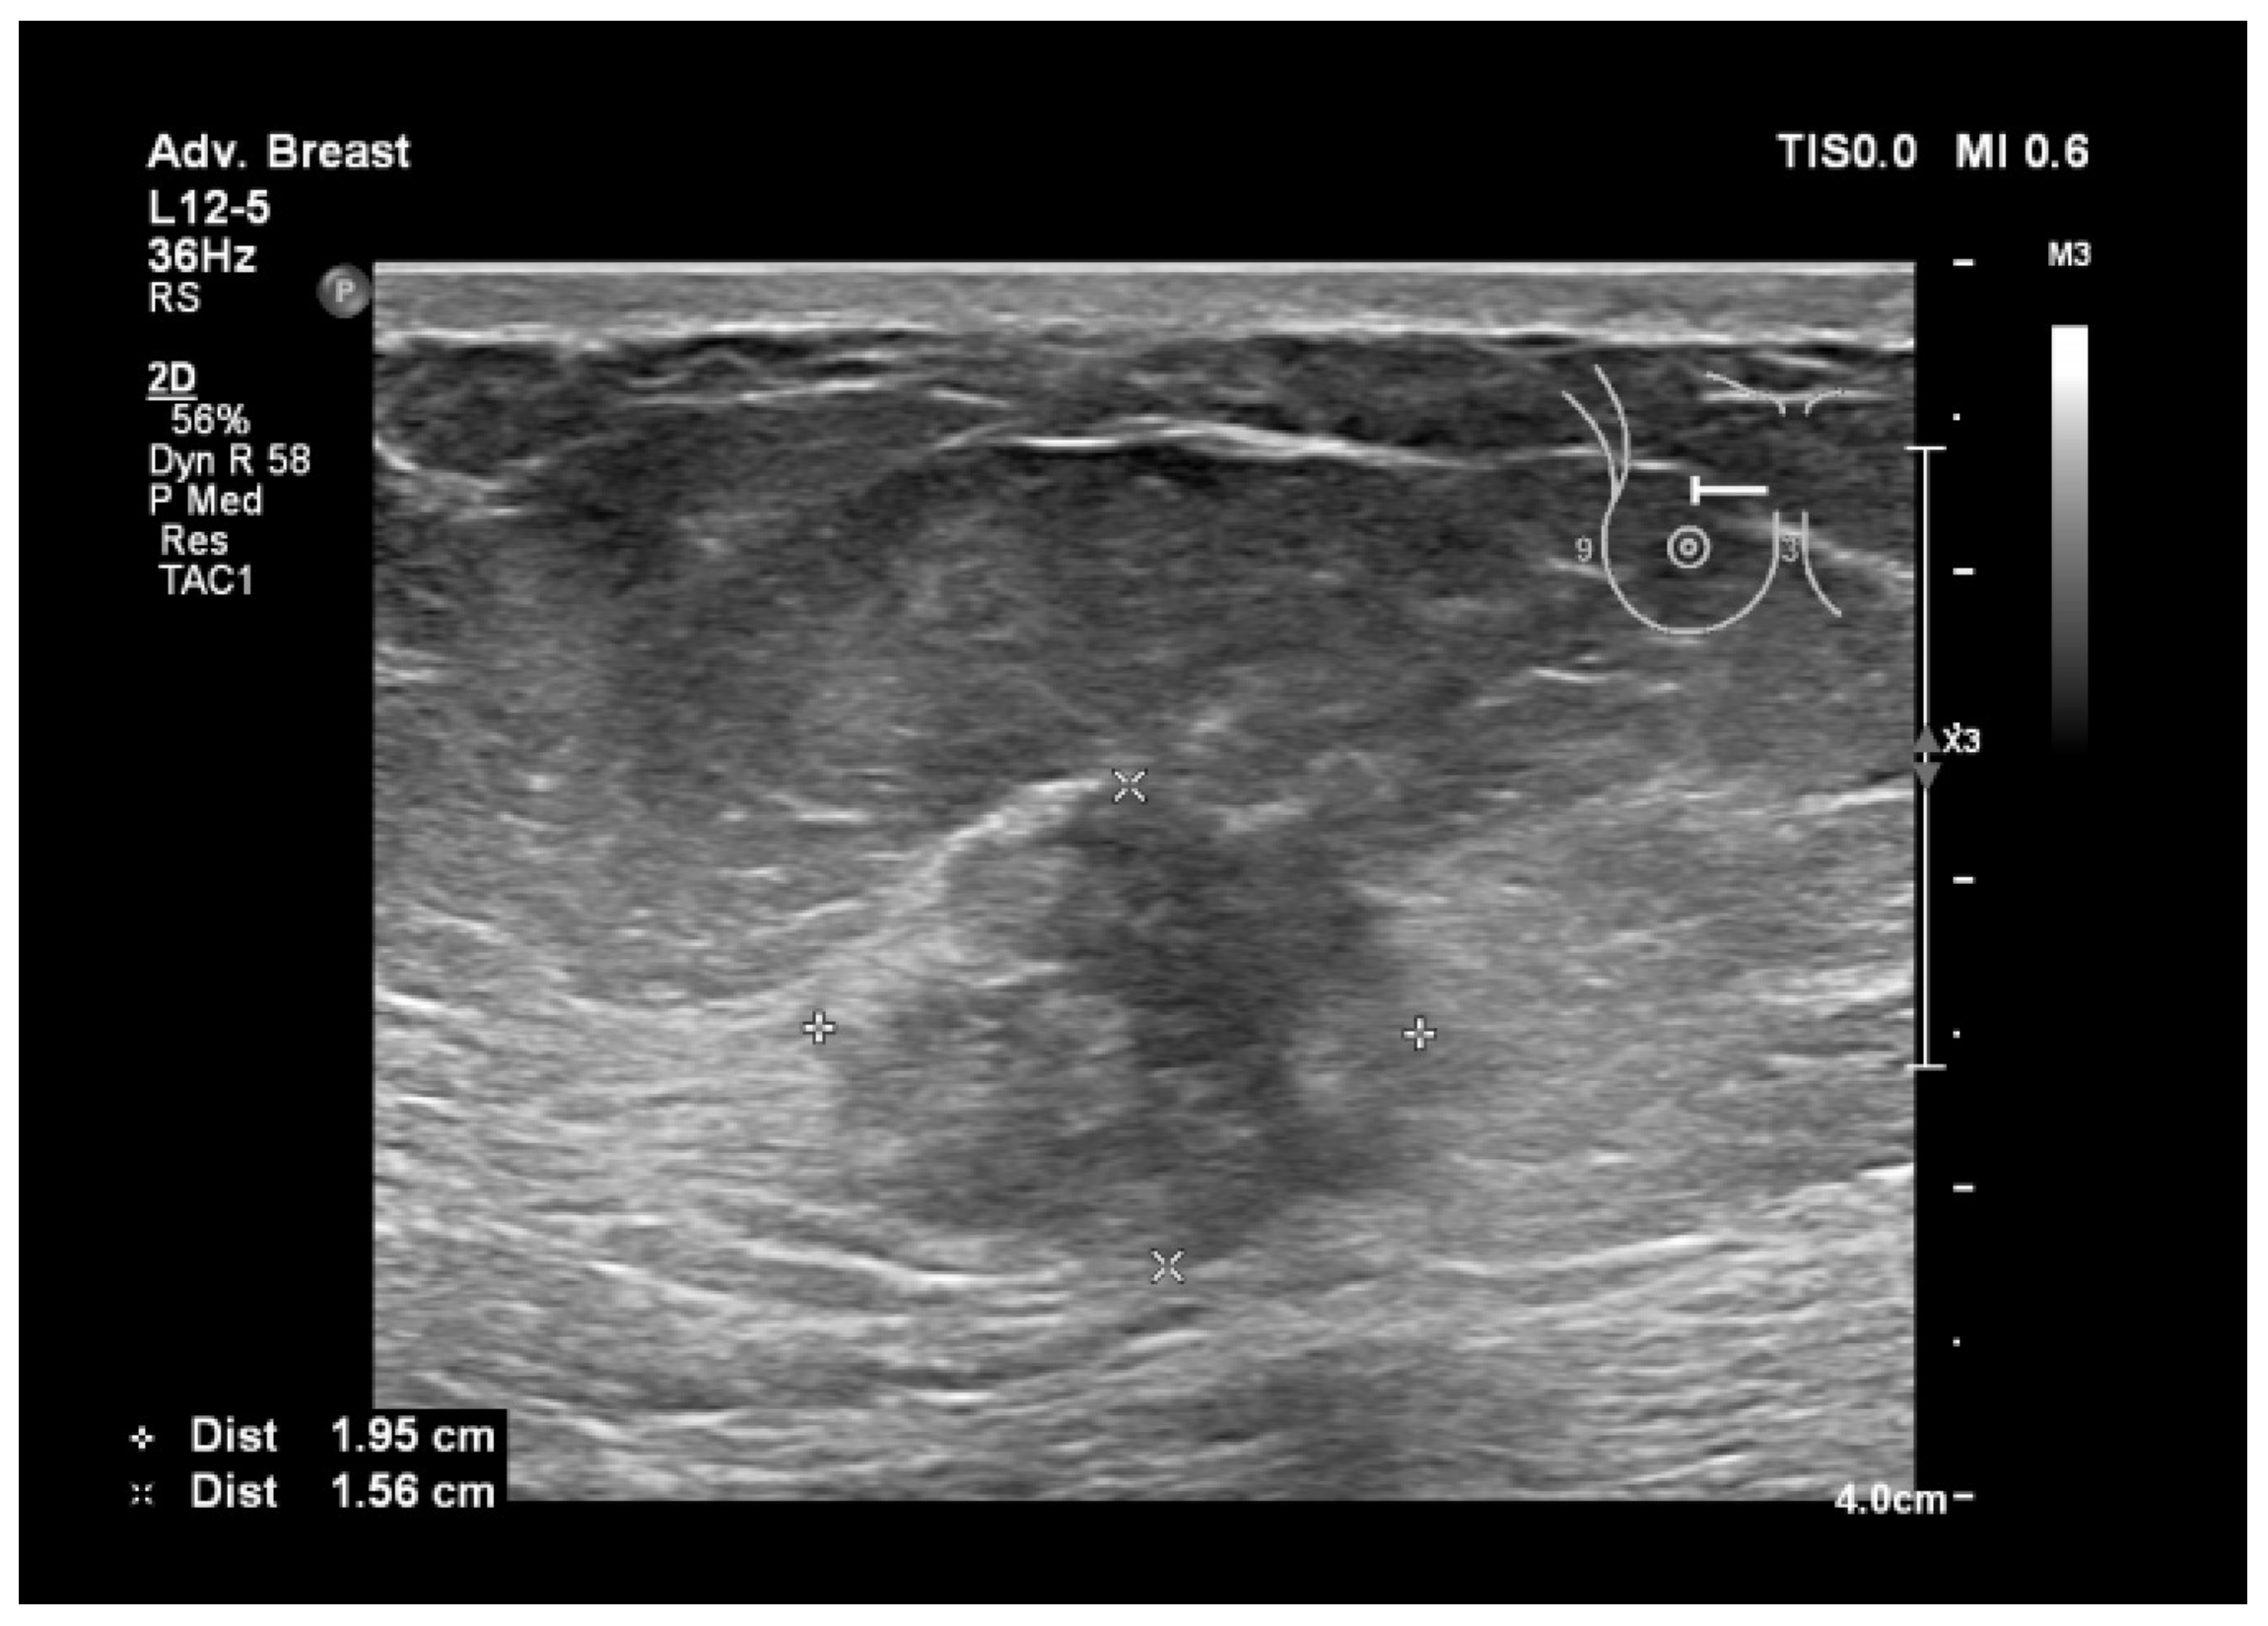

6.1. Characterization of Lesions

6.2. Real-Time Imaging and Guided Biopsies